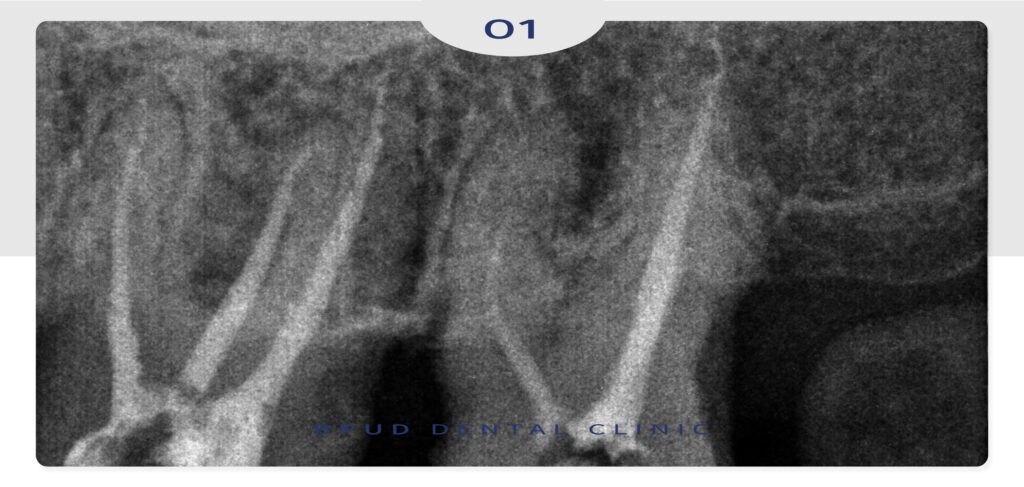

더불어 왼쪽 위 어금니의 경우에는

살려쓸 수는 있지만 많이 정출되어 있어

신경치료 후 크라운 수복 계획을 수립하였습니다.